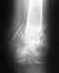

Дорого времени суток, уважаемые врачи! Болело в районе нижней трети левого бедра. В течении года, грешил на сустав коленный. Но боль усиливалась, и стала не выносимой. Сегодня сделали рентген, обнаружили патологию. Что это такое сказать не могут. Посмотрите снимок, пожалуйста. Что это можно быть??? Заранее спасибо!